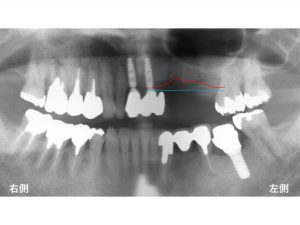

初診時のレントゲンが以下です。

上顎左側に歯が3歯欠損されている方です。

他の部位にはすでにインプラント治療が行われていた方です。

元々の骨の状態が以下の青線です。

本来骨はここまであったのです。

そして現在は以下の赤線まで骨が吸収してしまったのです。